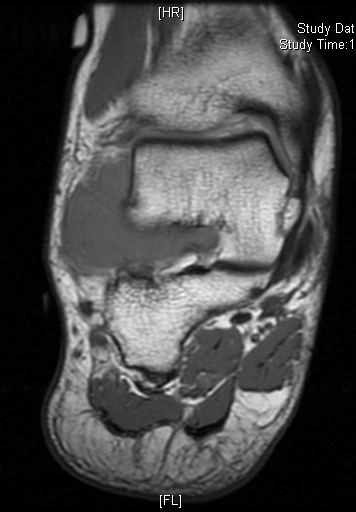

MRI

Shows multiloculated, heterogeneous mass.

“Triple Signal Intensity sign”; hypointense, isointense and hyperintense with fat on T2 – weighted MRI imaging. This sign is present in 30 to 50% of the cases. (Fig.3)

Under contrast enhancement Synovial Sarcoma appears heterogeneous and demonstrate areas of nodular enhancement.

In approximately 30% of cases a multiple vascular cannel may be identified

Synovial sarcomas may have a cystic appearance and are often mistaken for ganglion cysts especially those adjacent to tendons and in the foot and ankle.